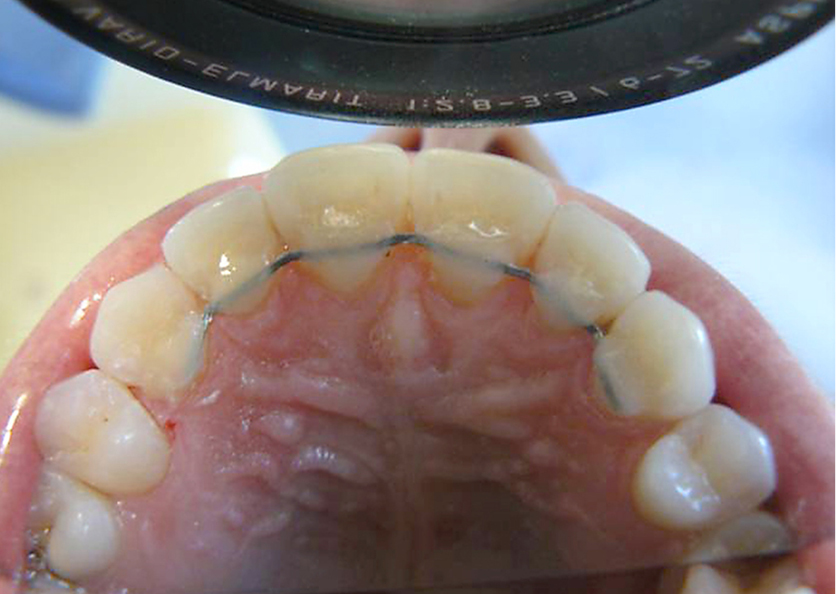

Streszczenie: Wstęp. Publikacje ortodontyczne ostatnich lat wskazują na konieczność długotrwałego utrzymania uzyskanych wyników leczenia za pomocą aparatów stałych. Pacjenci, decydując się na leczenie ortodontyczne, bardzo często nie są świadomi, że po zdjęciu aparatów ortodontycznych niezbędna jest kontynuacja leczenia aparatami retencyjnymi. Celem systematycznych kontroli w okresie retencyjnym jest zapobieganie nawrotom wad zgryzu i zmian w ustawieniu zębów. Najczęściej stosowanymi aparatami retencyjnymi są retainery stałe, które składają się z kilku spiralnie skręconych drutów ze stali sprężystej, a ich średnica, zależnie od producenta, waha się w granicach 0,4-0,5 mm. Przyklejane są do zębów najczęściej za pomocą światłoutwardzalnych materiałów kompozytowych. Dobór metody klejenia retainerów stałych jest dowolny. Istnieje możliwość klejenia metodą bezpośrednią lub pośrednią. Cel pracy. W pracy zostaną przedstawione odległe wyniki uzyskane ze stosowania retainerów stałych klejonych metodą pośrednią.

Materiał i metodyka. Badaniem objęto 72 pacjentów po leczeniu aparatami stałymi noszących retainery przyklejone metodą pośrednią. Każdy z retainerów został wykonany z drutu czworokątnego Bond-a-Bride firmy Reliance. Jest to miękki, płaski drut składający się z 8 splecionych nitek stalowych o wymiarze 0,673 mm [...]